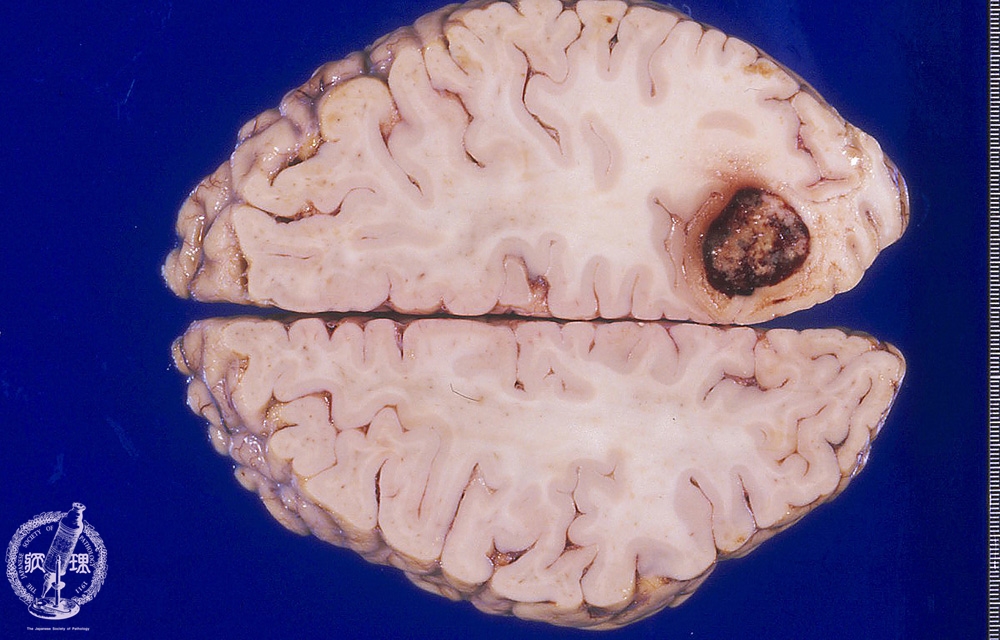

Macroscopic findings of brain metastasis from lung cancer. There was a large well-circumscribed round-shaped tumor in the right occipital lobe. Dark hemorrhagic foci were seen within the tumor and mild edema was identified around the tumor.